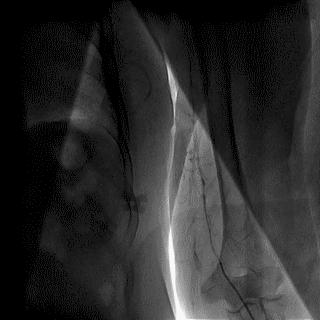

2014年,Patel T等首先采用球囊辅助通过技术(Balloon-assisted tracking,BAT),用于通过桡动脉途径中扭曲、细小节段(包括严重痉挛节段)(图1-2)。

图1

图2 BAT技术应用实例1。52岁女性患者冠脉严重痉挛(A),注射2次鸡尾酒后仍未缓解(B),采用BAT技术(C),顺利介导7F指引导管通过桡动脉严重痉挛节段(D)